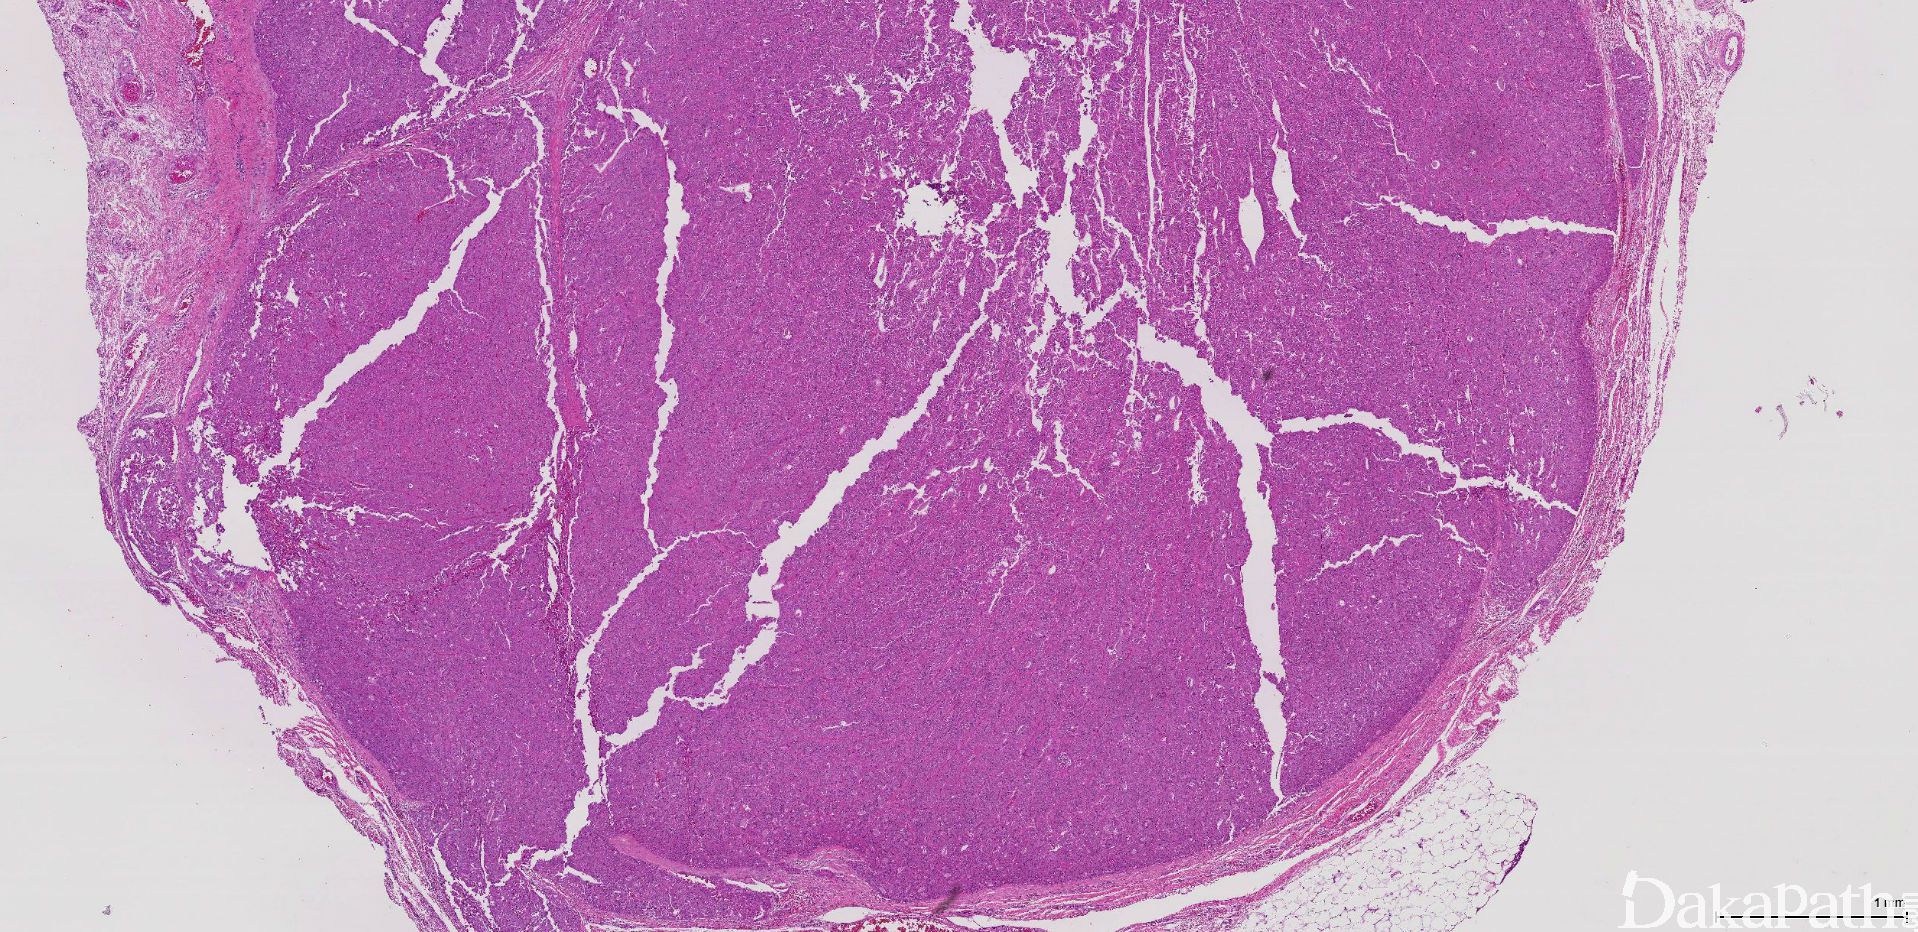

1. 有不同的形态特征,从分化很好的滤泡结构到实性和/或梁状结构;

2. 肿瘤细胞胞浆深嗜酸性颗粒状,细胞核浓染和多形,一般有显著的嗜酸性核仁;

5. 包膜和/血管侵犯是诊断的依据:

6. 包膜侵犯要求穿透纤维性包膜,包膜内细胞巢或索不作为包膜侵犯的依据;

8. 根据包膜侵犯的程度,滤泡性癌分为两个亚型:微小浸润和广泛浸润,但目前没有统一的诊断标准,有学者建议肉眼不能识别的包膜浸润为微小浸润,肉眼能识别的浸润为广泛浸润。